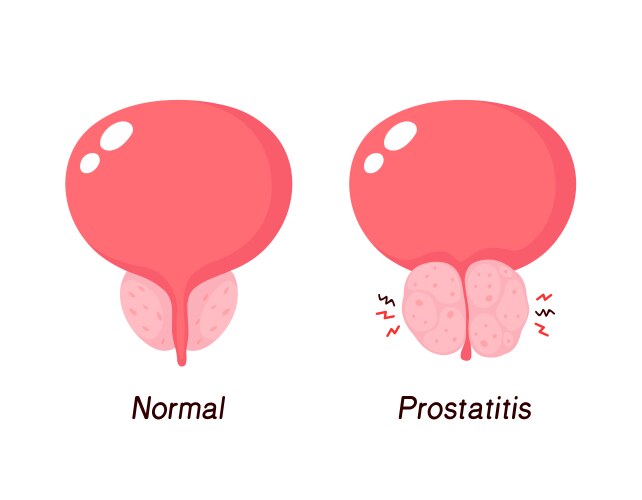

- Prostatitis

- Swelling

- Inflamed

- Pain